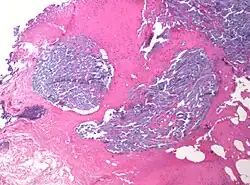

Micrographs of loose, moderate and dense desmoplastic stroma in pancreatic ductal adenocarcinoma, as seen with H&E stain (top row), Masson's trichrome stain (middle row) and α-smooth muscle actin.